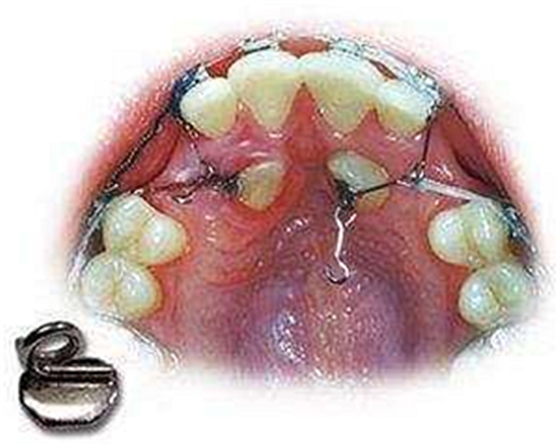

牙齒牽引就是正牙過程中的一個(gè)步驟。是要把長的不規(guī)范的牙齒借助外力,牽引到正確的地方。

什么是 牙齒牽引?